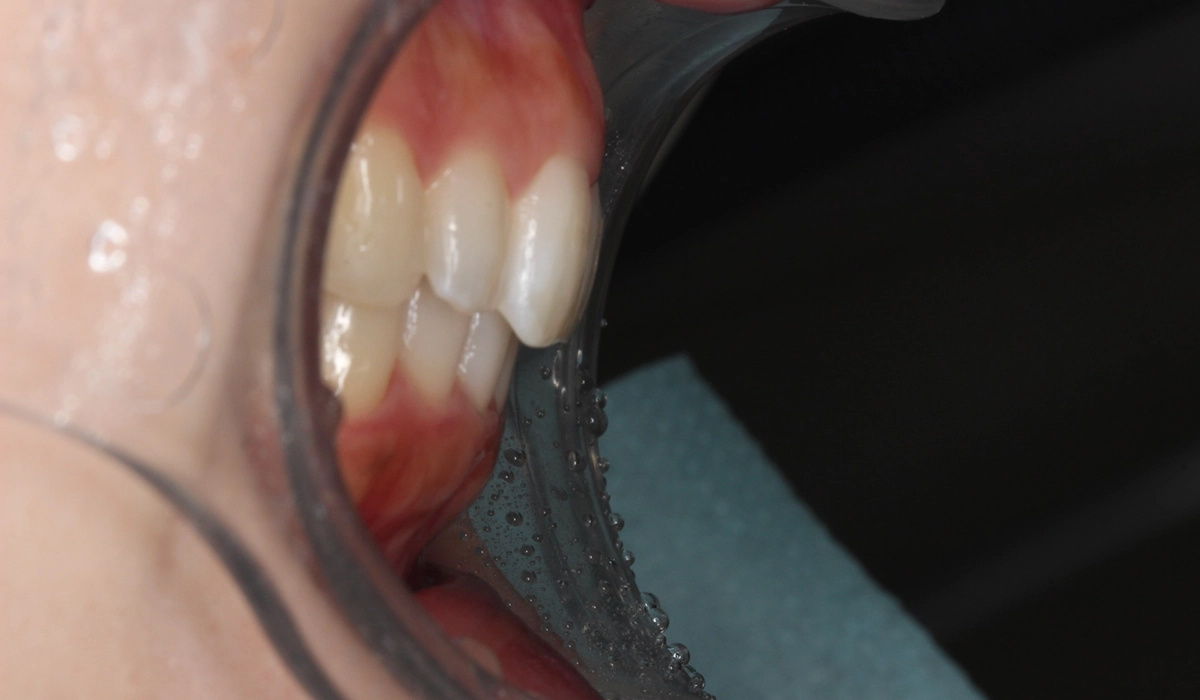

術前:右側

術後:右側

術前:左側

術後:左側